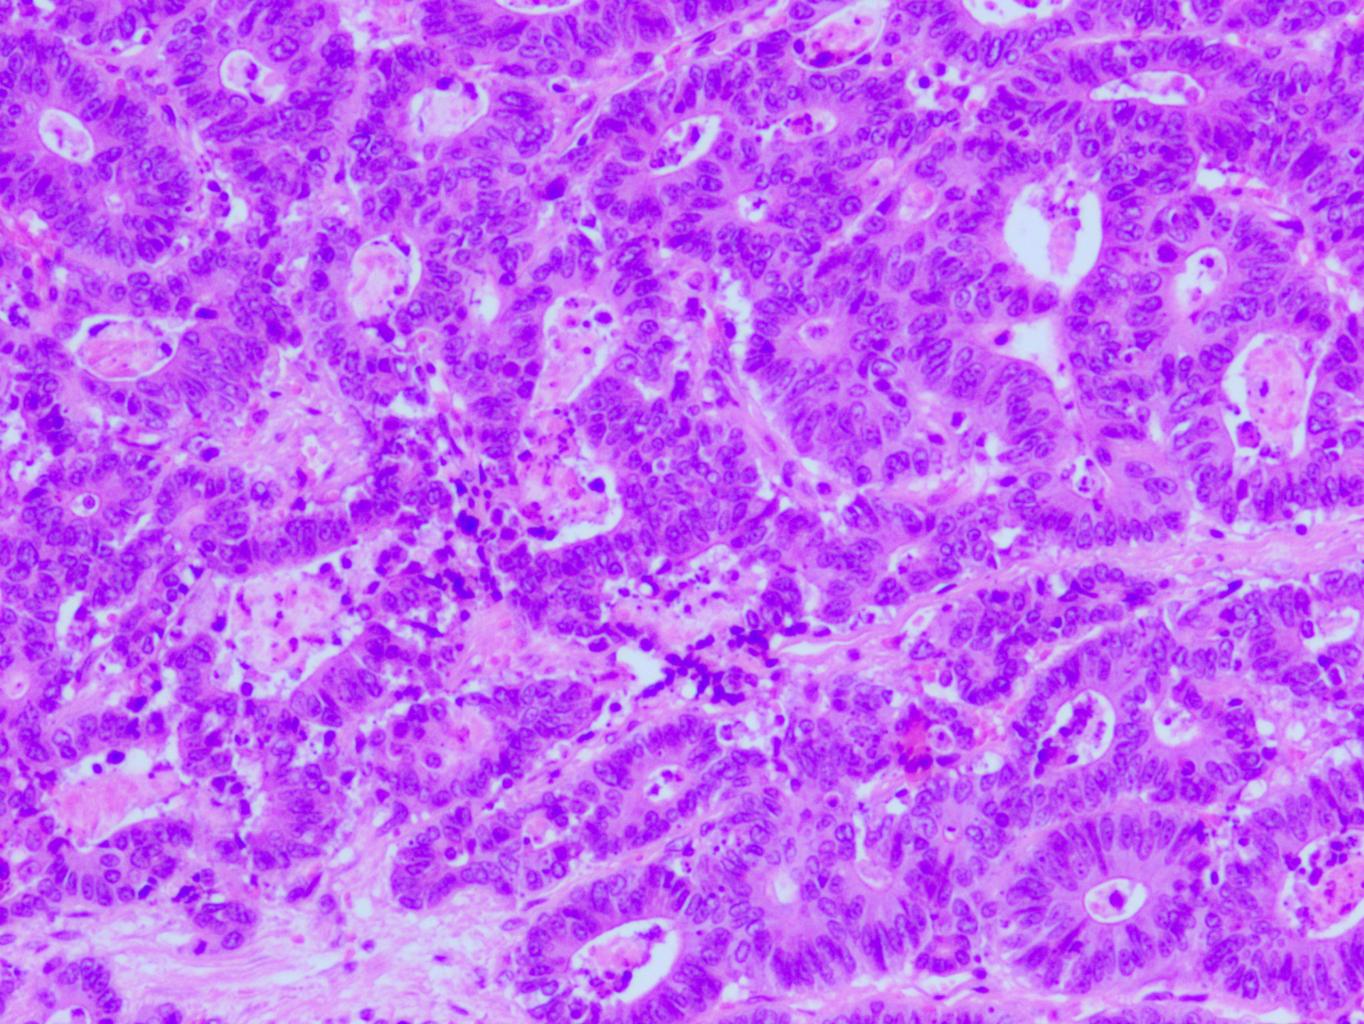

Resnās zarnas adenokarcinoma hematoksilīna eozīna krāsojumā. Foto: Inese Briede

Viens no faktoriem, kas var ietekmēt ļaundabīgu audzēju progresiju, ir iekaisums, kas sekmē audzēja šūnu augšanu, jaunu asinsvadu veidošanos un invāziju apkārtējos audos. Iekaisuma šūnu izdalītās bioloģiski aktīvās vielas sekmē audzēja šūnu pārveidošanos, tām iegūstot mezenhimālām šūnām raksturīgās īpašības, ko dēvē par epiteliāli mezenhimālo transformāciju. Patoloģijā šo procesu raksturo audzēja šūnu virsmā lokalizētie antigēni CD44, E-kadherīns, N-kadherīns, B-katenīna un citi.